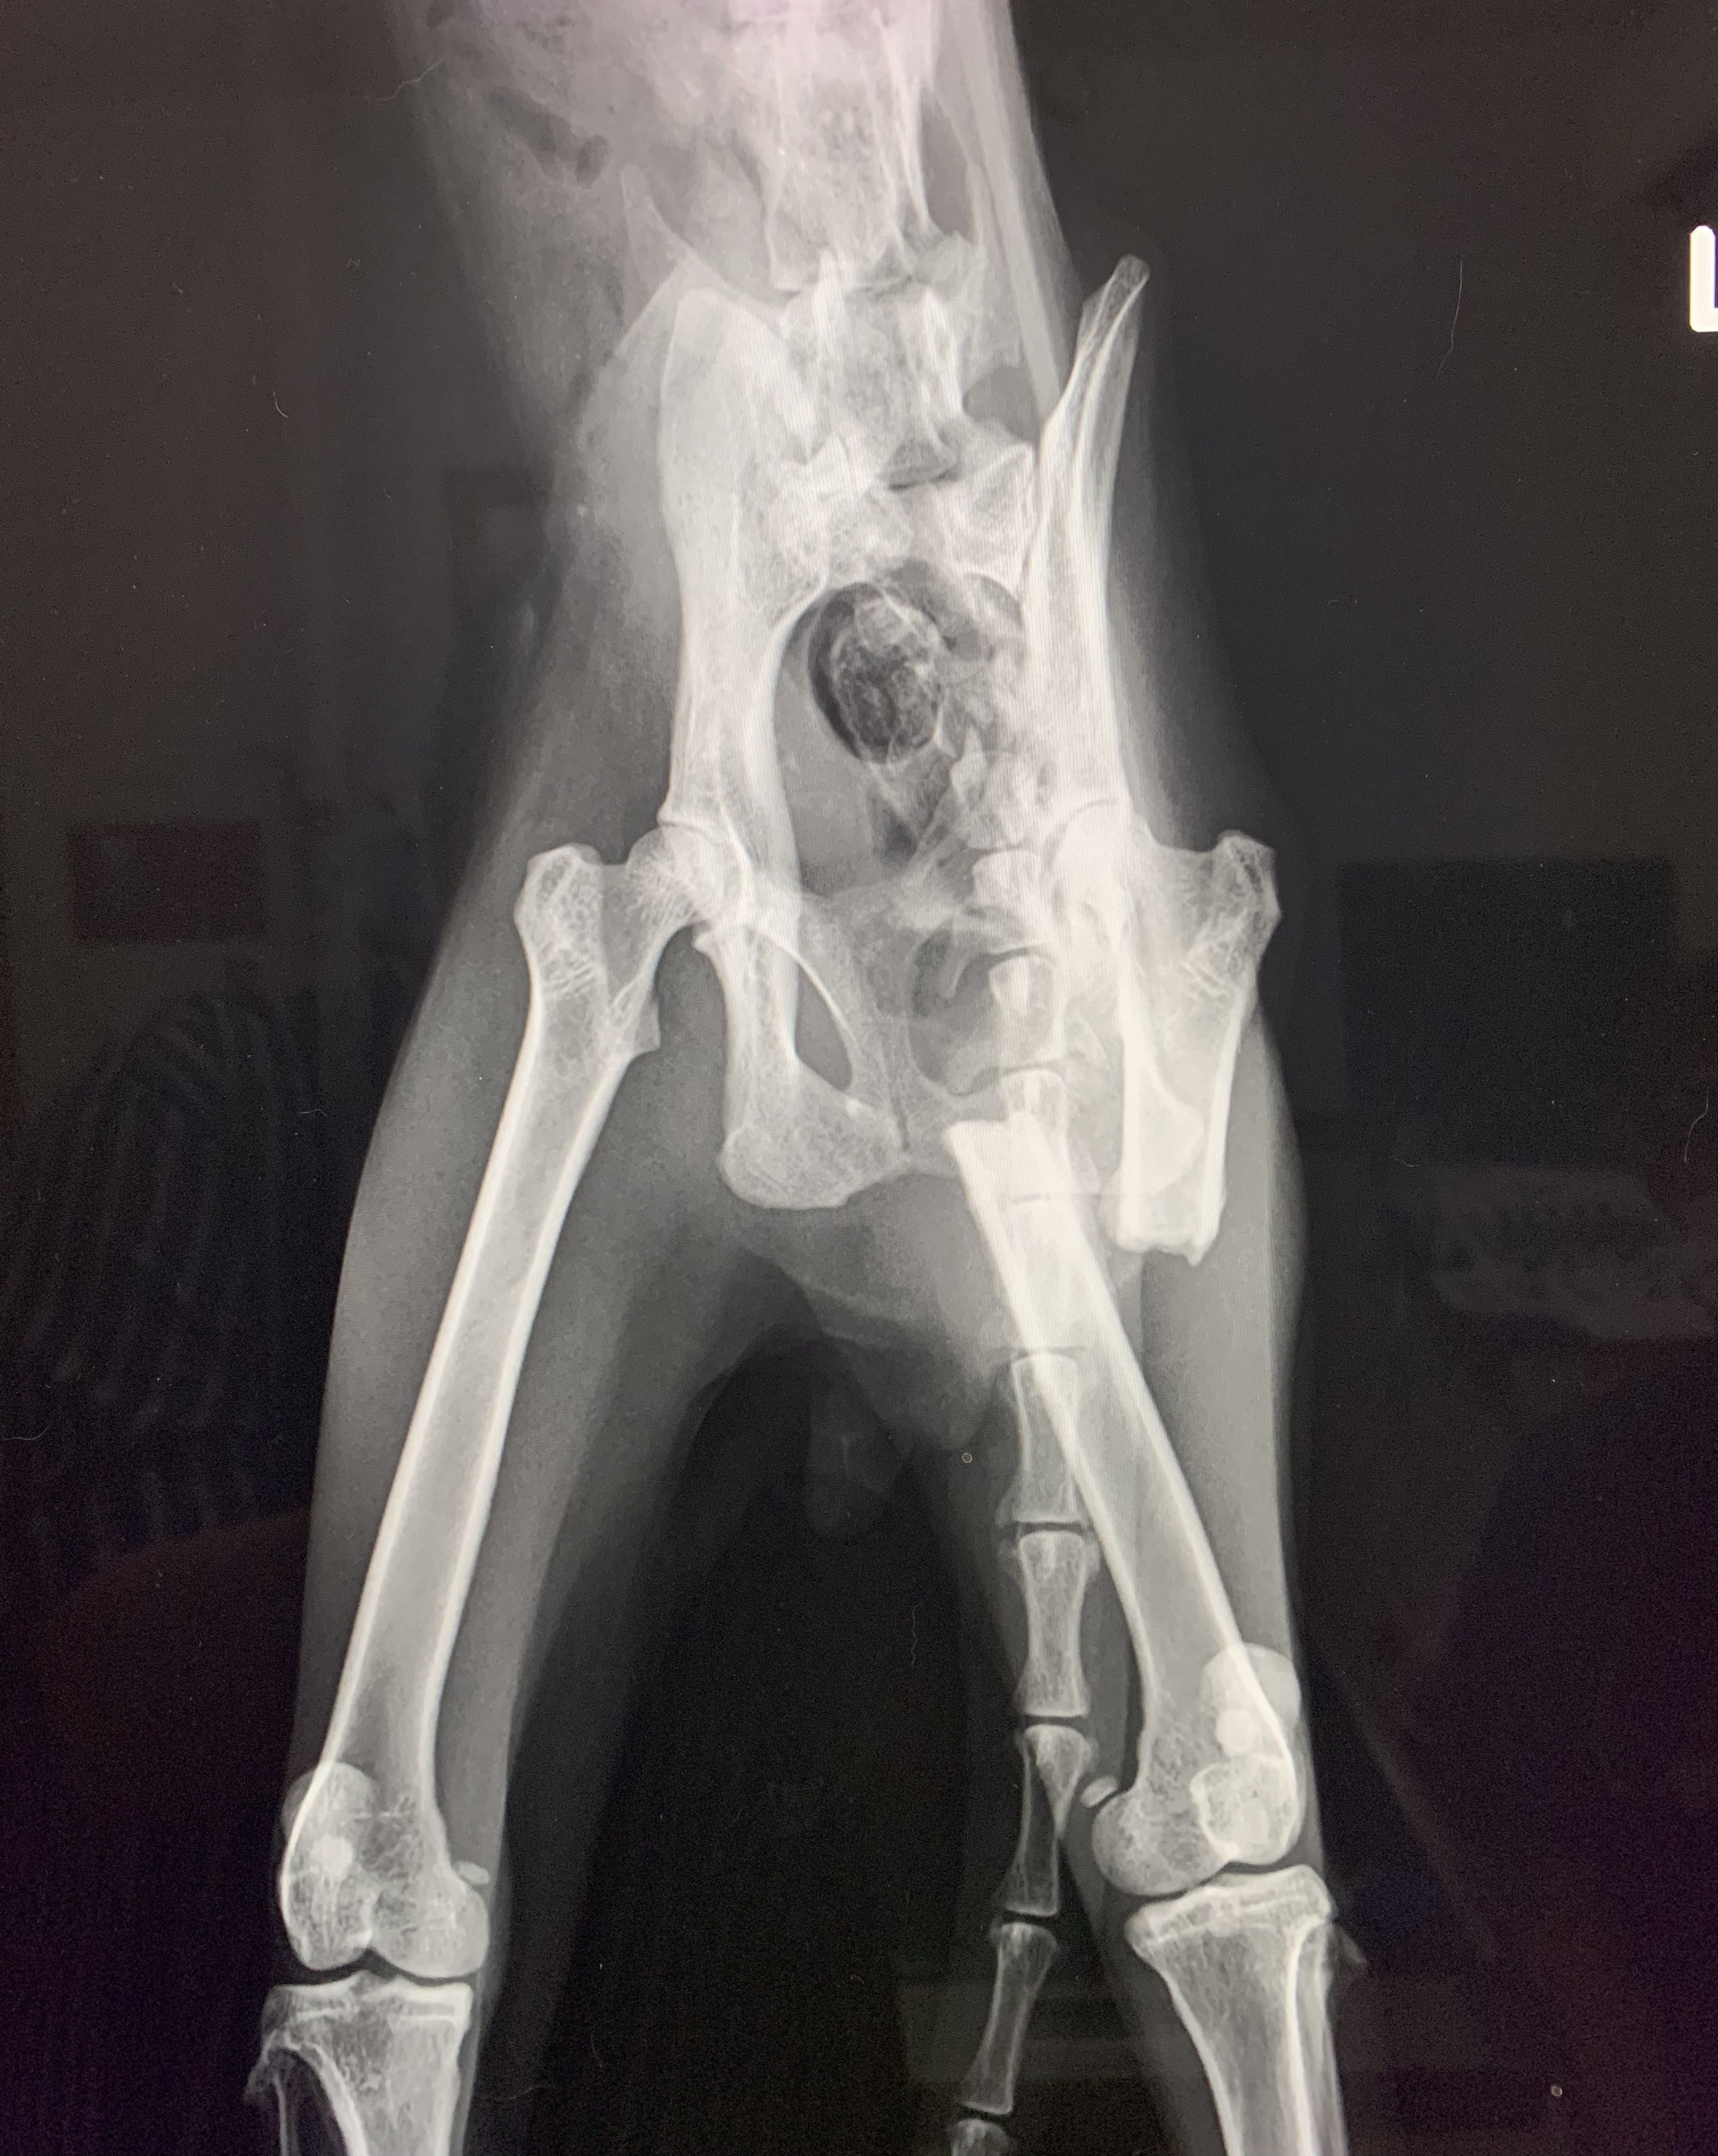

翌朝、動物病院での診断は、左大腿部の骨折!しかも骨折から数ヶ月が経過しており、それを補うための筋肉が発達したせいで、骨折した部分が筋肉により引っ張られ、左右に離れていました。このまま放置を続ければ左足の膝が逆向きになり重度の障害が残る大変な状況であることがわかりました。また、推定3歳の雄猫ですが、体重はわずか2キロしかありませんでした。